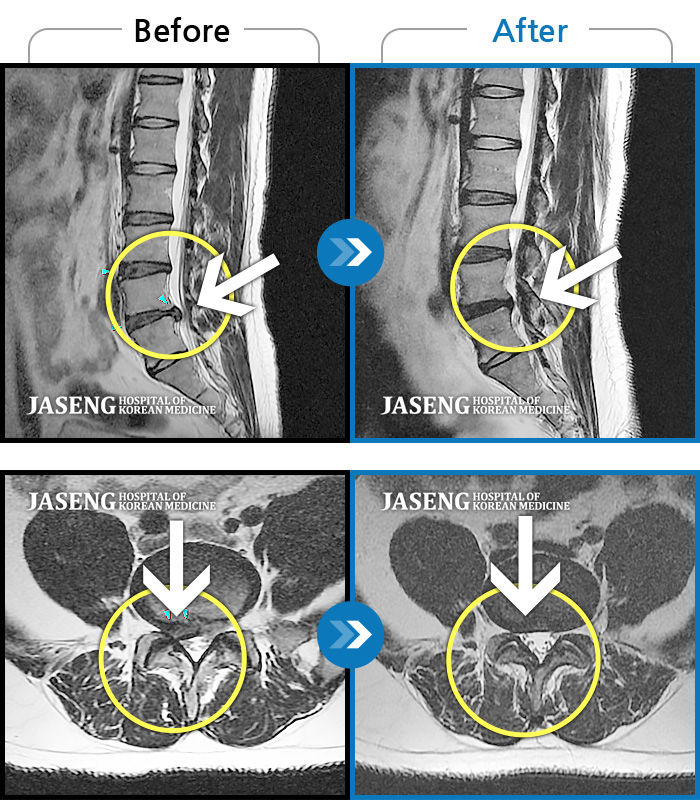

허리디스크

보라매 · 빈상은 원장

엉치에서 좌측 다리 뒤쪽으로 통증과 저림이 매우 심해요.

촬영시기

2024.06.08 ~ 2024.08.31

2024.12.24

조회수 459